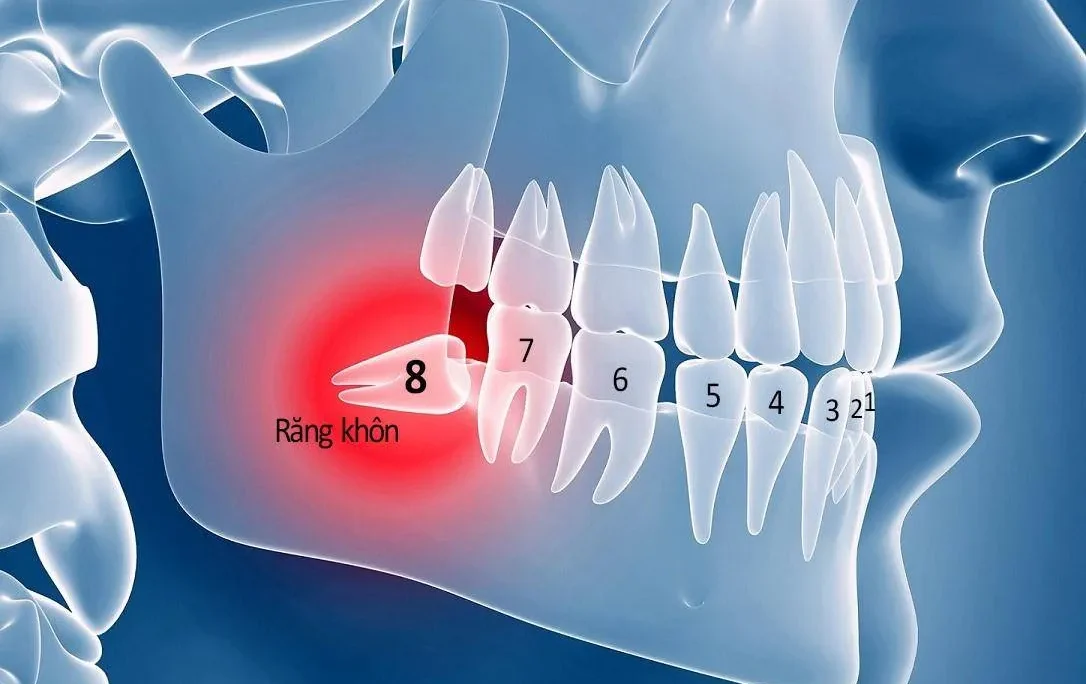

Niềng răng là phương pháp chỉnh nha sử dụng các khí cụ chuyên biệt để thực hiện. Các khí cụ này bao gồm mắc cài, dây cung hoặc khay niềng. Khi đeo khí cụ, mắc cài và dây cung sẽ tác động lực tác động liên tục lên răng. Từ đó làm cho di chuyển các răng sai lệch về đúng vị trí trên cung hàm. Phương pháp này rất hiệu quả trong việc điều chỉnh các tình trạng răng mọc lệch. Ví dụ như hô, móm, khớp cắn sâu, răng khấp khểnh, khớp cắn chéo. Cùng với đó là khắc phục nhiều vấn đề sai lệch cấu trúc hàm khác

Không kể mức độ nặng nhẹ, niềng răng có thể áp dụng cho mọi trường hợp răng thưa. Kết quả sau quá trình niềng răng là một hàm răng đều đẹp, khớp cắn hoàn hảo. Đồng thời bảo toàn tuổi thọ cho răng mà không ảnh hưởng đến cấu trúc của răng và hàm. Phương pháp niềng răng không gây đau và không xâm lấn.

Ngoài ra, niềng răng cũng là sự lựa chọn của nhiều người bởi sự an toàn và hiệu quả. Đặc biệt, niềng răng cực kì tốt khi khe răng thưa do thiếu răng vĩnh viễn. Tuy nhiên khu vực mầm răng phía dưới vẫn còn. Đây là phương pháp an toàn và hiệu quả nhất để đưa răng mọc ngầm trở về vị trí đúng trên khung hàm.